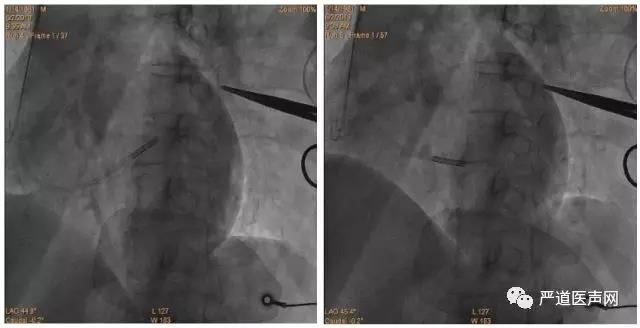

手术过程:

行冠状静脉造影后选择侧静脉为靶血管,经腋经脉植入电极导线,心房电极植入右心房心耳,右心室电极植入中低位室间隔,左室电极植入冠状静脉侧分支,术中测试左心室阈值2.5V,感知15mV,阻抗680Ω;右心室 阈值0.75V,感知20mV,阻抗580Ω。出院后心电图显示QRS波时限138ms。 CareLink远程随访显示患者动态BIV起搏比例99%,AV间期一直动态优化,术后5个月心脏超声提示EF 52%,几乎与正常人相同。5个月后患者回医院随访,自述目前心功能明显改善,可以正常生活,饮食睡眠良好,期间没有因为心衰再住院治疗。

分别为:造影、AP、LAO45°